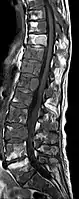

IRM natif avec pondération T1.

IRM sagittal natif avec pondération T1. On voit clairement l’extension jusqu'aux lames vertébrales.